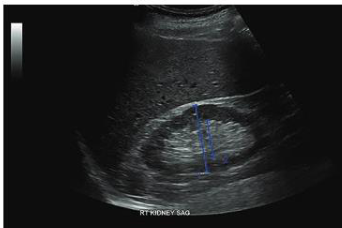

name that pathology -Dilation of the renal pelvis, calyceal structures, and infundibula by urine -Obstruction can be either intrinsic or extrinsic -Sonographic “hallmark” - splaying, spreading, or ballooning of the central echo complex -Dilated ureter helpful in differentiation

HYDRONEPHROSIS

Accounts for majority of palpable abdominal masses in neonate

HYDRONEPHROSIS May be caused by Ureteropelvic Junction Obstruction, Posterior Urethral Valves, or by compression of the ureter